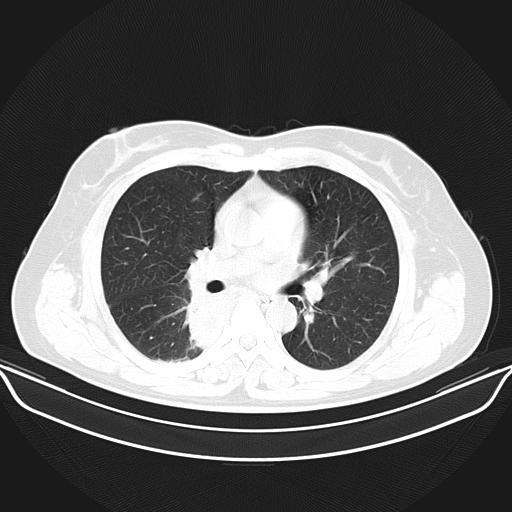

标题: CT22224:肺部肿块

f,48,主因咳嗽咳血来我院检查,无发热。

1)右肺下叶背段团块状软组织密度影;建议抗炎治疗后复查排除肿瘤性病变。2)右侧少量胸腔积液。

谈一谈个人的看法:机器性能应该不错,可惜扫描方法不太正确,即没有及时薄层扫描图像,也没有增强检查,这样的检查方法不正确的图片拿来研究只能是猜一猜:右肺下叶阻塞性改变,建议进一步检查删除肺癌。

支气管镜检查未见异性细胞,抗炎治疗20天,肿块明显缩小。